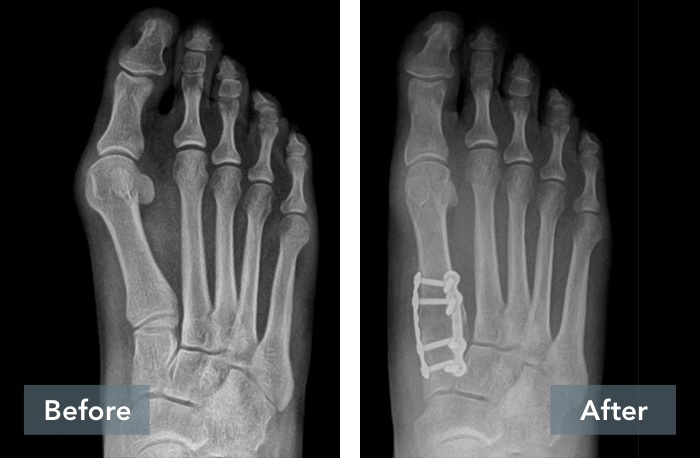

See the Results

Lapiplasty® Before & After Results

A common misconception is that a bunion is simply a “bump” that can be “shaved off.” But, bunions are more than a bump – they are complex 3D problems caused by an unstable joint in the middle of the foot. While the majority of bunion surgery is only 2D and fails to address the root cause, Lapiplasty® provides a 3D correction and secures the unstable joint.

While traditional 2D osteotomy surgery merely cuts & shifts the bone to address the cosmetic bump, Lapiplasty® 3D Bunion Correction™ does more — it corrects the entire bone in 3D and secures the unstable foundation to get you back on your feet quickly in a walking boot. The Lapiplasty® Procedure has also shown low recurrence; 97% and 99% maintain 3D correction in 13 and 17 months respectively.1,3